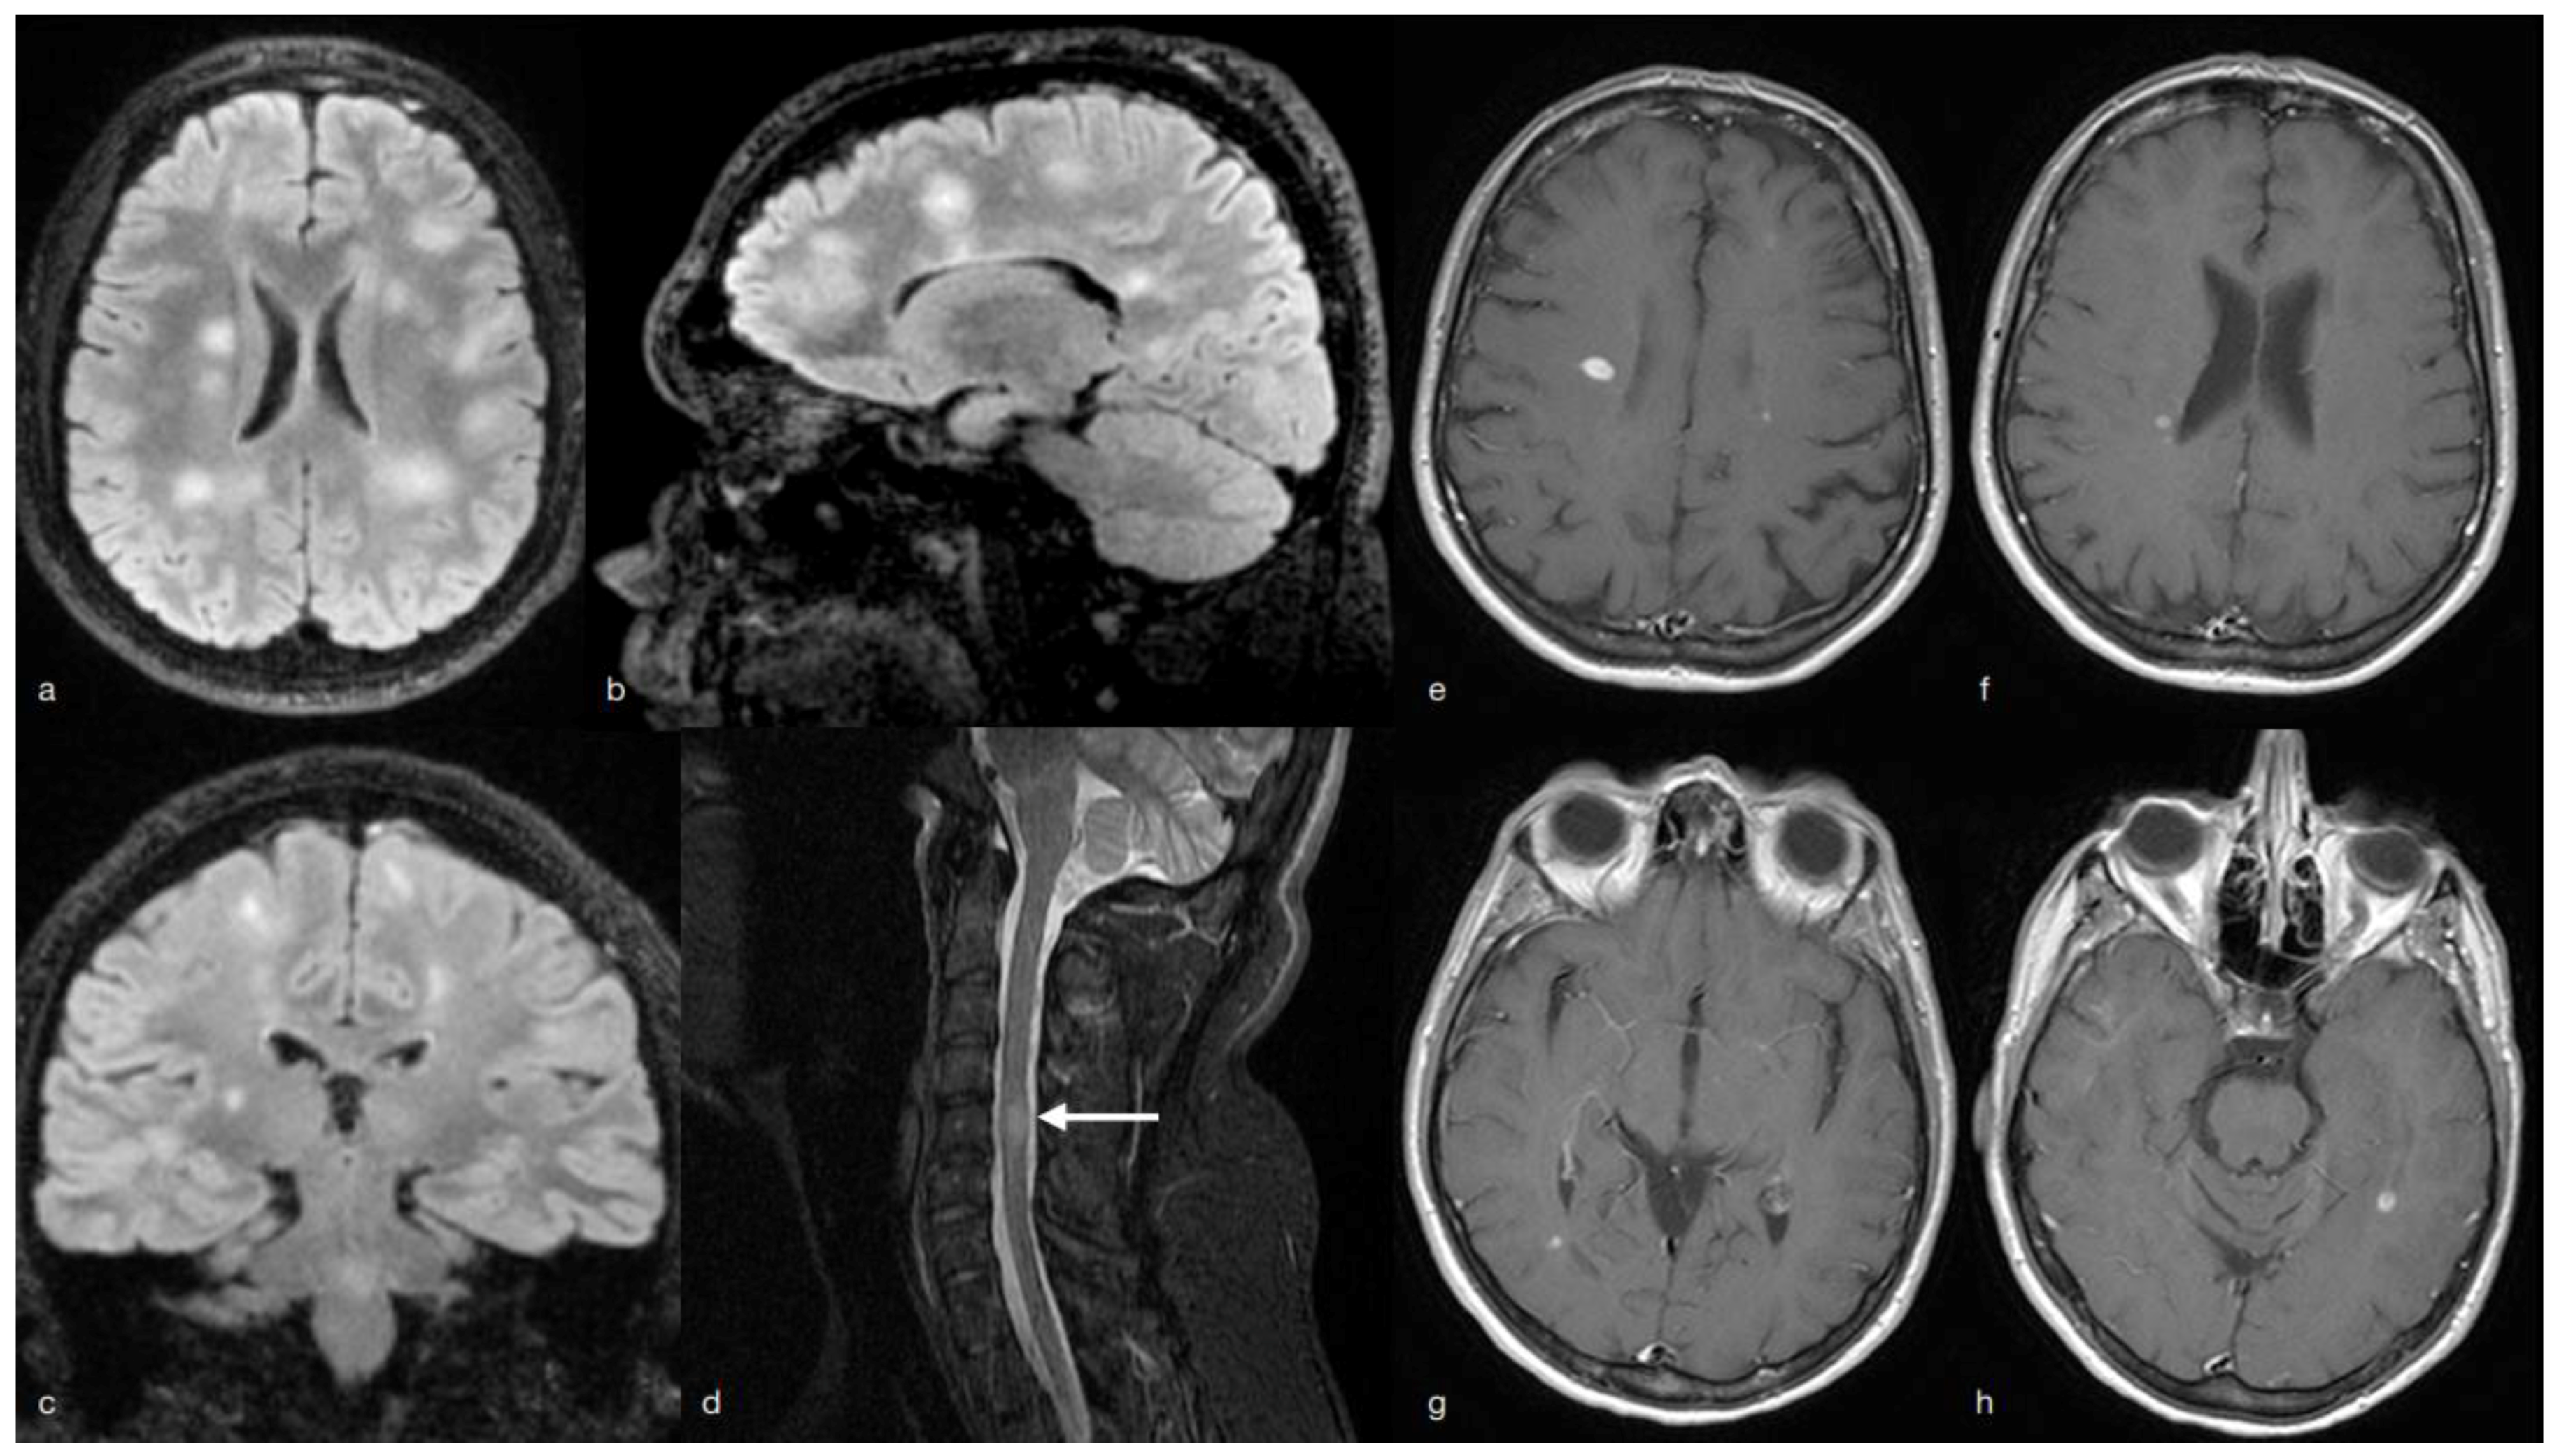

2. MS Onset

3. Multiple Sclerosis (MS) Relapse